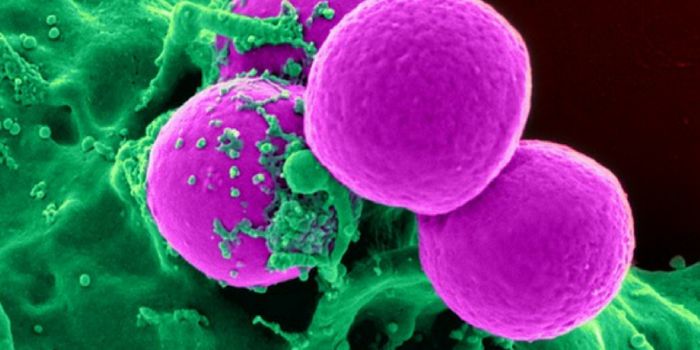

SEP 17, 2021Cell & Molecular BiologyMRSA (methicillin-resistant Staphylococcus aureus) is a well known superbug, a pathogenic microbe that can cause serious ...